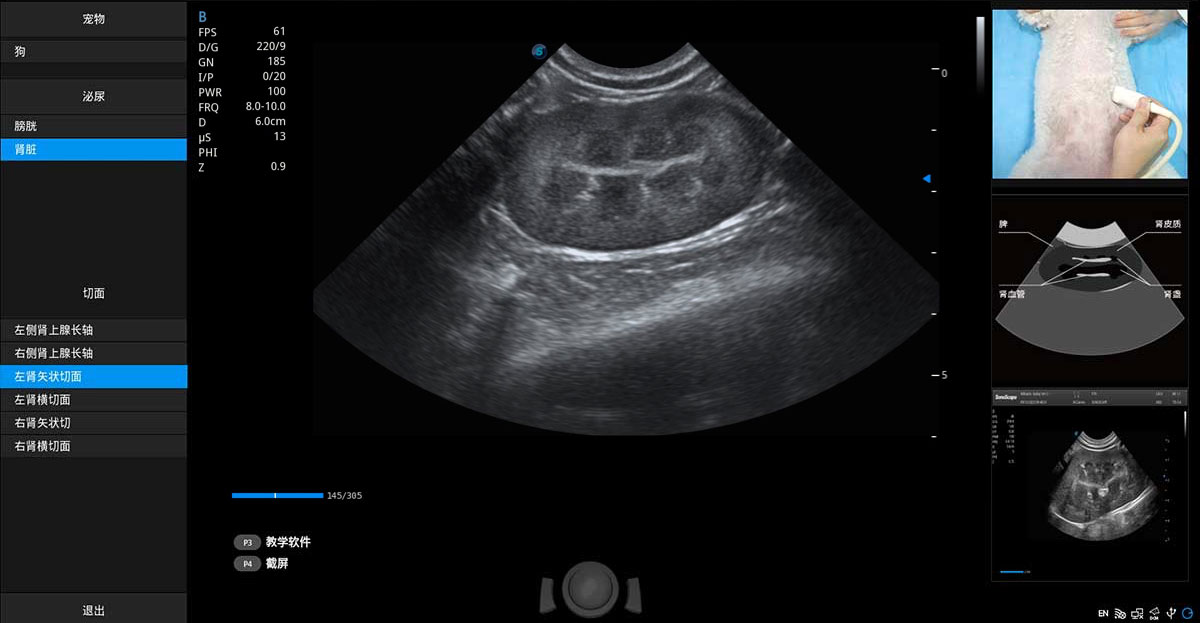

ProPet 70专为动物医生设计,对不同的动物体型和生理结构作出了针对性的优化。通过动物影像专用软件,可满足个性化的应用需求,帮助动物医生获得更精确的诊断数据。

提供解剖示意图、标准超声图像、扫查手法图和操作者实时检查图像,指导操作者进行标准切面的正确扫查。